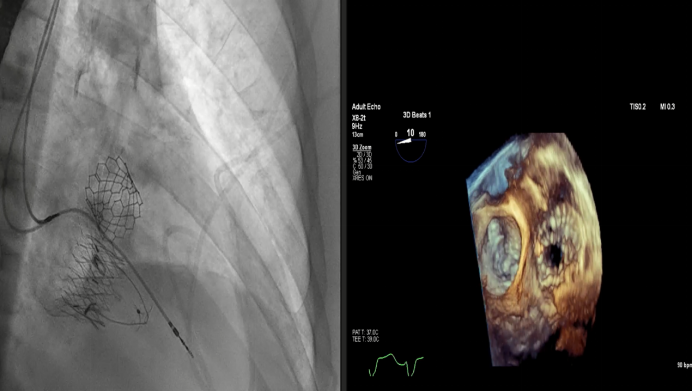

Dee Dee Wang教授分享了Henry Ford Hospital前4例Lux-Valve Plus的植入經(jīng)驗(yàn),并提示術(shù)中確定瓣葉夾持鍵的位置處于三尖瓣瓣環(huán)下方(右心室側(cè)),以及室間隔固定片與室間隔的相對(duì)位置關(guān)系是最關(guān)鍵的兩個(gè)步驟。使用經(jīng)胃底短軸切面,有時(shí)配合右室流入/流出道切面的X-plane就能較容易地獲取相關(guān)影像。由于Lux-Valve Plus對(duì)超聲影像的要求較低,手術(shù)過程會(huì)相對(duì)比較流暢。

術(shù)后結(jié)果